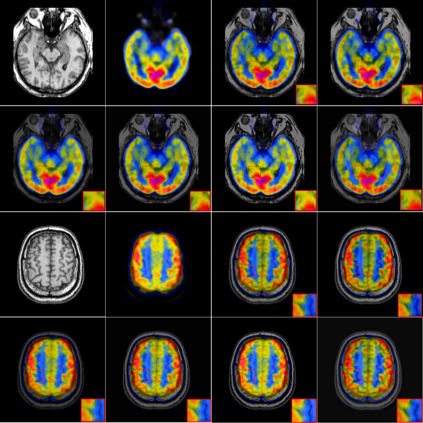

In recent years, various applications in computer vision have achieved substantial progress based on deep learning, which has been widely used for image fusion and shown to achieve adequate performance. However, suffering from limited ability in modelling the spatial correspondence of different source images, it still remains a great challenge for existing unsupervised image fusion models to extract appropriate feature and achieves adaptive and balanced fusion. In this paper, we propose a novel cross attention-guided image fusion network, which is a unified and unsupervised framework for multi-modal image fusion, multi-exposure image fusion, and multi-focus image fusion. Different from the existing self-attention module, our cross attention module focus on modelling the cross-correlation between different source images. Using the proposed cross attention module as core block, a densely connected cross attention-guided network is built to dynamically learn the spatial correspondence to derive better alignment of important details from different input images. Meanwhile, an auxiliary branch is also designed to model the long-range information, and a merging network is attached to finally reconstruct the fusion image. Extensive experiments have been carried out on publicly available datasets, and the results demonstrate that the proposed model outperforms the state-of-the-art quantitatively and qualitatively.